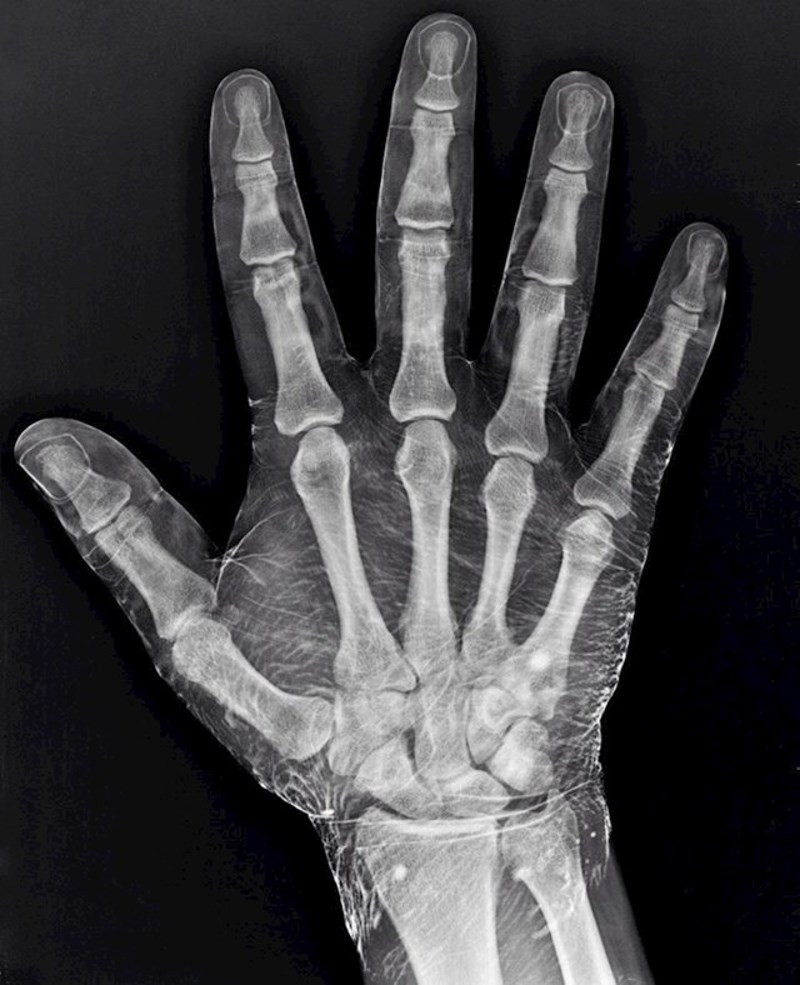

2. Rendgenska slika ruke umočene u jod. Jod utječe na sliku tako što prikazuje i mesnato tkivo oko kostiju.